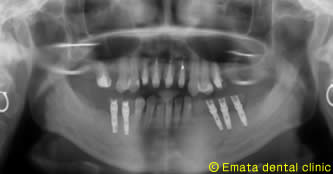

入れ歯は絶対いやなので、インプラント治療をご希望されました。恐怖心が強かったのですが、麻酔医専門医の協力のもと静脈鎮静法を併用してインプラント治療だったのでとても楽とうことでした。このあと左上の奥歯に骨造成(サイナスリフト)をしてインプラント治療を行う予定です。